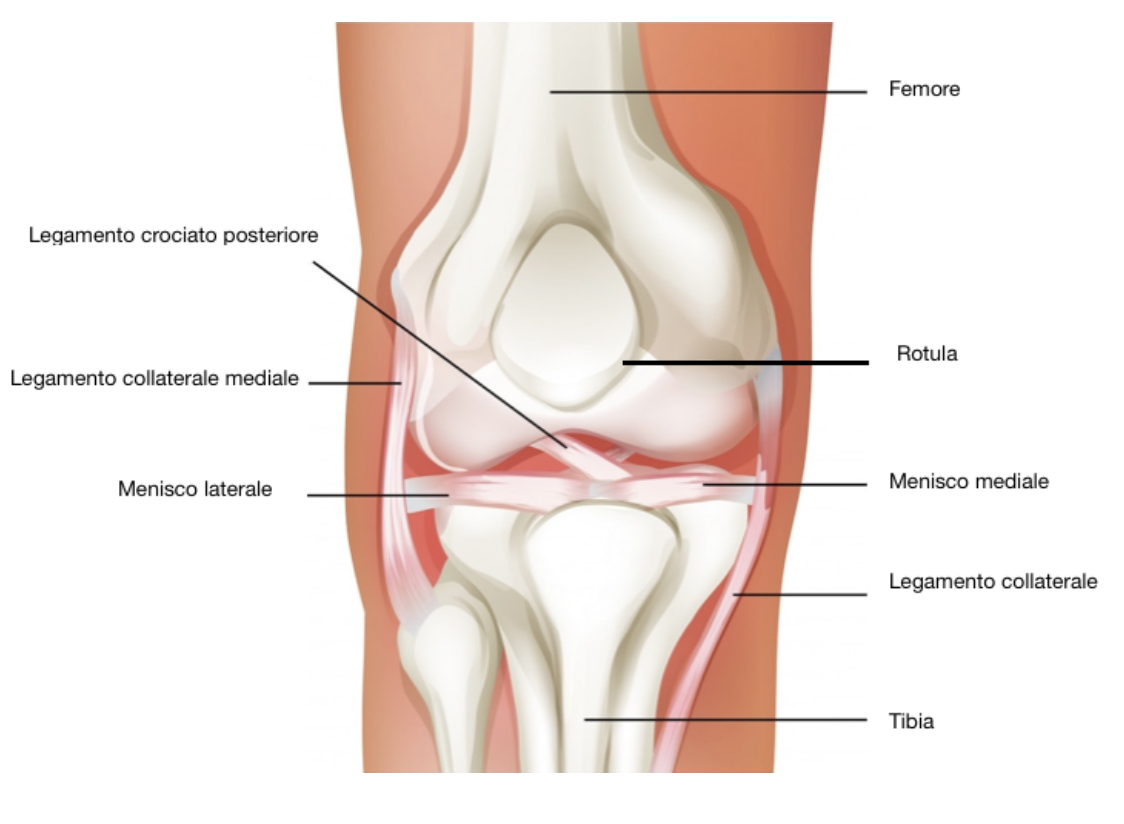

Il ginocchio è un’articolazione che unisce la coscia e la gamba, insieme al piedi compongono gli arti inferiori. E’ caratterizzata da grande mobilità ed ha come scopo l’estensione della gamba.

Posta tra tibia e femore è la più ambia del corpo umano, ha un’anatomia complessa composta da:

• Cartilagine articolare: (la sua funzione e la concordanza dei campi articolari riducendo l’usura di questi ultimi);

• Membrana sinoviale: (produce il liquido sinoviale, utile alla lubrificazione interna del ginocchio);

• Tendini e legamenti: (garantiscono la stabilità dell’articolazione);

• Borse sinoviali: (sacche ripiene di liquido simile a quello della membrana);

• Menisco mediale e laterale: (strutture fibro-cartilaginee che fungono da ammortizzatori).